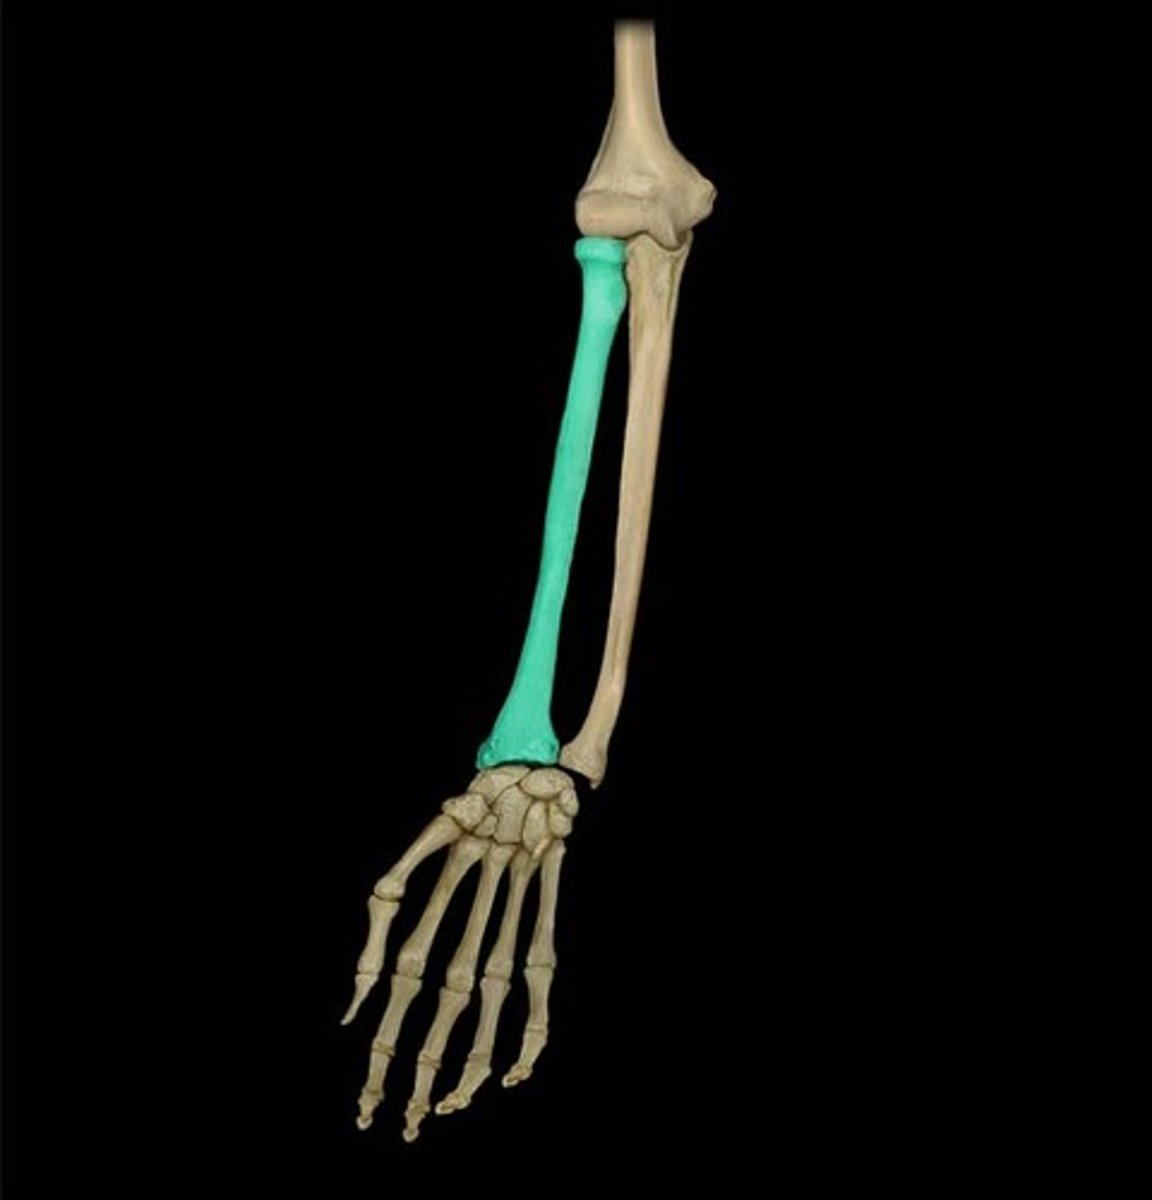

Radius

lateral bone of the forearm, in line with the thumb

Ulna

Inner and larger bone of the forearm, attached to the wrist and located on the side of the little finger.